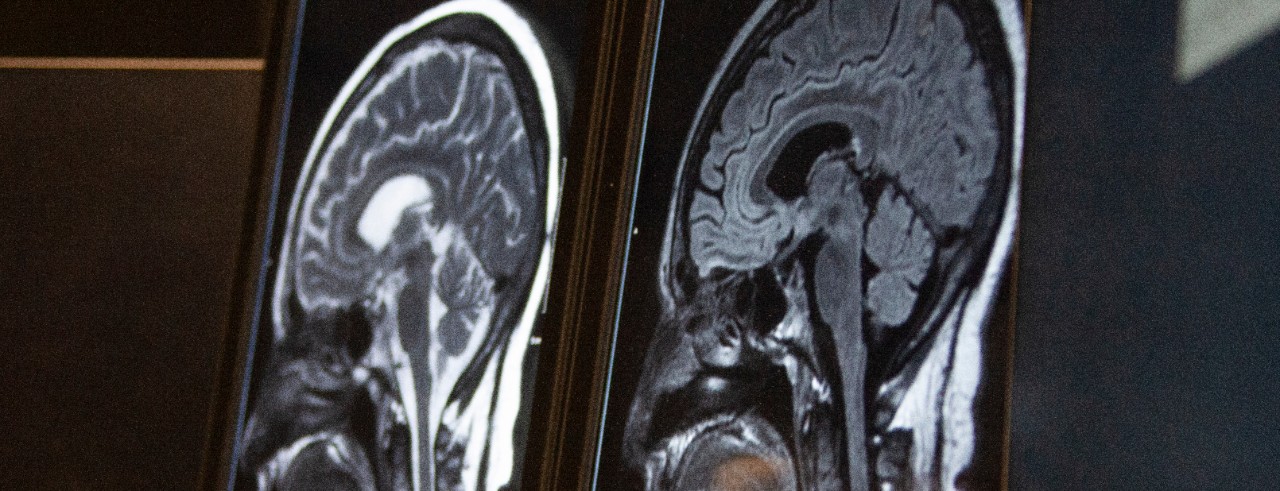

Featured photo at top of MRI brain scan. Photo/Ravenna Rutledge/University of Cincinnati.